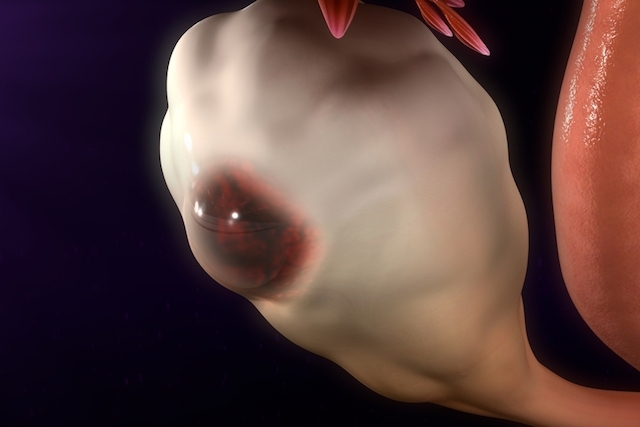

De caráter crônico e ainda sem causas definidas, a endometriose vem crescendo em números de casos na população feminina, sendo classificada como a doença da mulher moderna. O endométrio é a parte interna do útero que cresce todo o mês à espera de uma gravidez e quando isso não acontece, esse local descama e a mulher menstrua. Se o endométrio está dentro da cavidade, podemos identificar uma situação normal, mas se ele sai da cavidade uterina e infiltra em outros locais do corpo feminino, como as trompas, ovário, intestino e bexiga, isso pode ser nominado como endometriose.

A endometriose pode interferir no processo de engravidar, mas quando a gravidez acontece, a gestação tende a evoluir de forma positiva. Quanto ao avanço da doença neste período, podem existir exceções, mas não é muito comum, pois a mulher grávida produz muita progesterona, uma substância que naturalmente bloqueia o endométrio. Ainda que apresente o comportamento infiltrativo, a endometriose é benigna e não tem possibilidade de se desenvolver como um tumor maligno. O diagnóstico precoce da doença aumenta as chances de se evitar as complicações do desenvolvimento dessa infiltração.